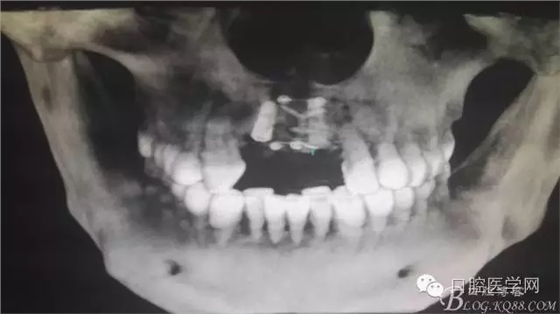

為他院轉(zhuǎn)診患者。男,無吸煙史,前牙因齲壞治療后,外力折斷導(dǎo)致拔除。現(xiàn)拔除該牙后兩個多月。 左上區(qū)域骨寬度不足,計劃植入種植體同期GBR。

左上區(qū)域骨寬度不足,計劃植入種植體同期GBR。